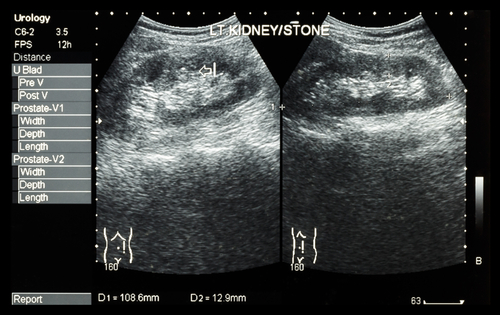

二卵性双胎の場合、妊娠5週ごろにエコー検査で胎嚢がふたつ確認できます。エコー写真では、ふたつの黒い楕円の部屋があり、それぞれに赤ちゃんが白い影として写っているのが見えるでしょう。

一方、心拍が確認できたころの一卵性双胎のエコー写真を見ると、ひとつの黒い楕円の部屋の中に、ふたつの白い影が写っているのがわかります。ただし、角度によっては白い影がひとつしか見えないこともあるようです。

エコー写真では、赤ちゃんを包む羊膜もうっすらと白い線として確認することができます。DD双胎の場合、ふたつの黒い部屋にそれぞれいる赤ちゃんを白い線が囲うように見えます。MD双胎の場合は同じ部屋にいる赤ちゃんがひとりずつ線に囲まれていて、MM双胎の場合はひとつの膜にふたりとも入っています。